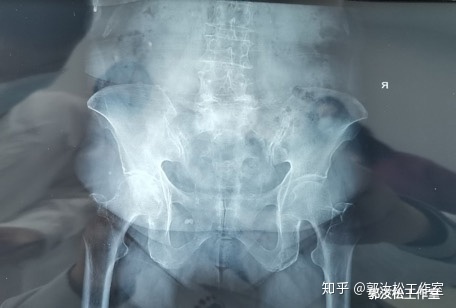

现病史: 患者10年前开始出现腰痛,无下肢不适,腰痛发作时自行外贴药膏或当地就诊药物治疗后缓解,未检查,未系统治疗。1年前患者腰痛反复发作,逐渐加重,同时伴有双下肢放射痛,走路逐渐跛行,平时仍自行外用药物外敷,或自行购买止痛药治疗,未到医院治疗。来诊前1周外院行腰椎X光检查提示腰椎退行性变,骨质疏松,L4、5椎体向前滑脱,L5达Ⅲ度滑脱。胃纳可,二便暂正常。

查体: 腰部肌肉稍紧张,L4、5可触及阶梯感,局部压痛,双下肢肌力5级,腱反射未见亢进,双下肢皮肤感觉基本正常,直腿抬高试验+。

// 影像科 :X光片 /// 就诊当天影像学检查

1.腰椎滑脱(L4椎体向前I度,L5椎体向前Ⅲ度)

2.腰椎间盘突出症

3.老年性骨质疏松症